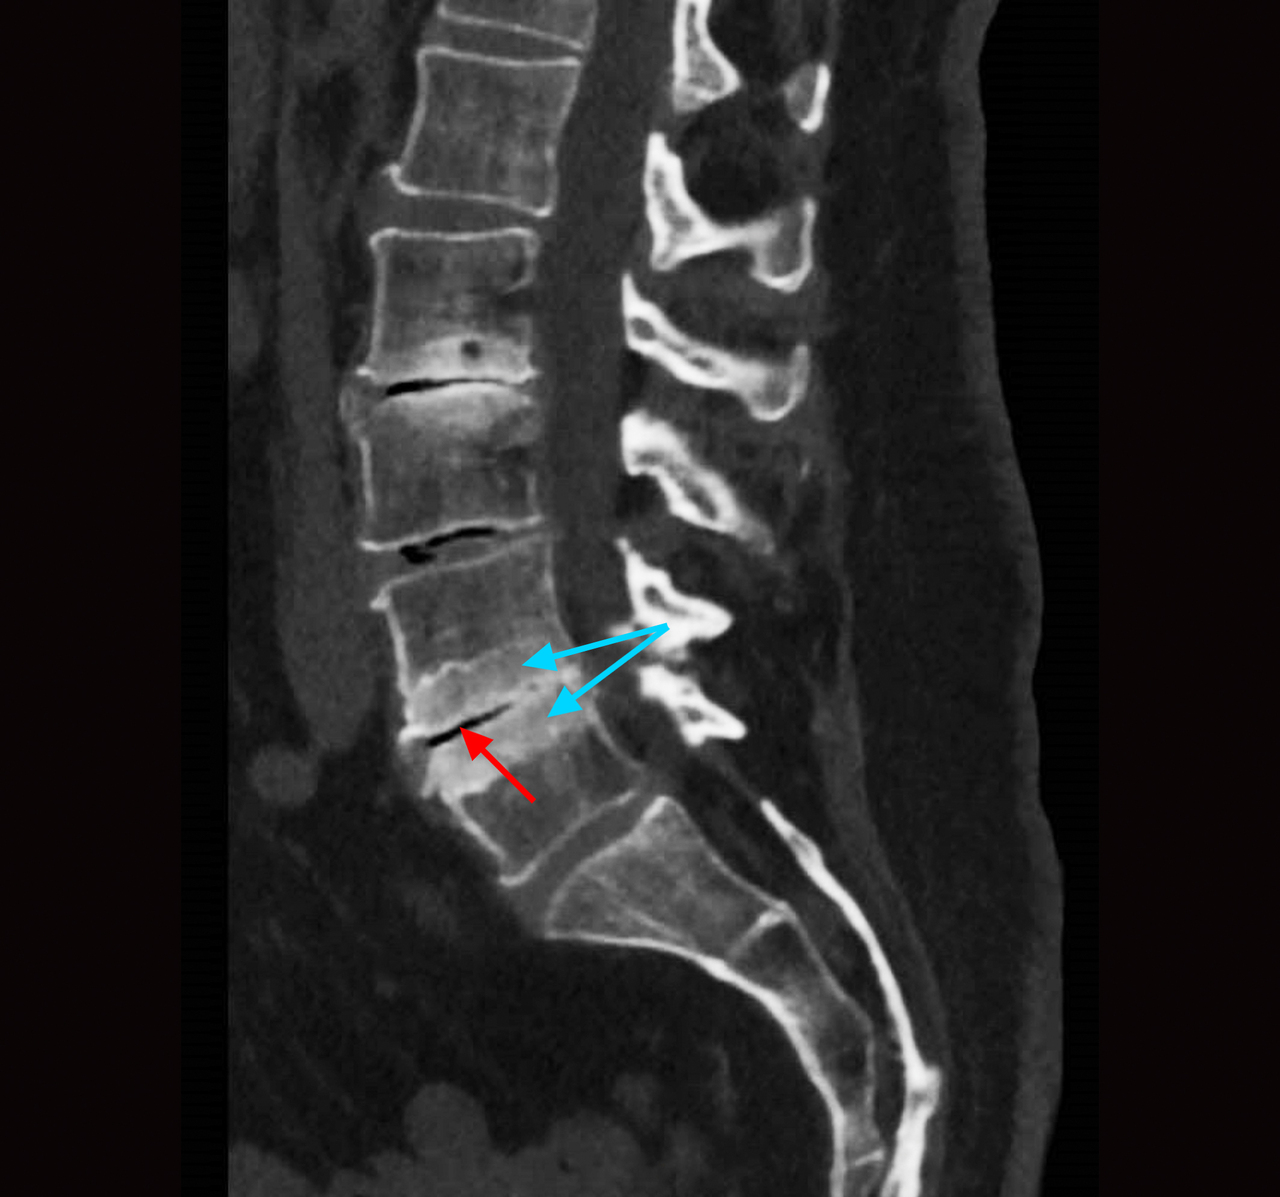

Le scanner montre une condensation des plateaux vertébraux (flèches bleues) et un aspect de « vide discal » (flèche rouge). L’atteinte discale et des plateaux vertébraux adjacents peut faire évoquer le diagnostic de spondylodiscite. Toutefois, l’absence de fièvre et de syndrome inflammatoire associée à l’image de « vide discal », à la condensation des plateaux vertébraux et à l’existence d’ostéophytes orientent vers une arthrose lombaire.